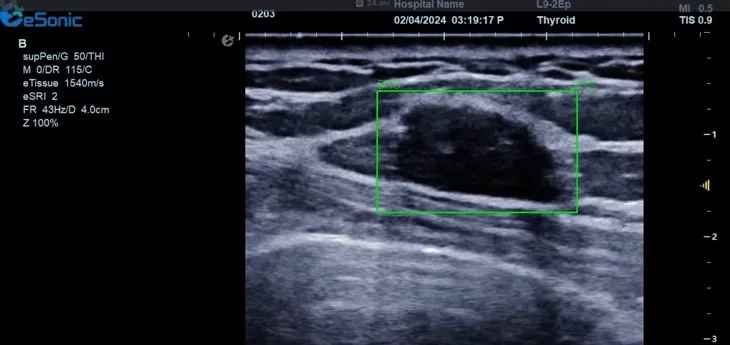

利来国国际网站医疗(ESI)表示,其最新的人工智能功能可以帮助到医疗机构的工作效率,功能包括,实时、动态、快速自动识别病灶,良恶性病灶概率预测,甲状腺结节和乳腺的二维灰阶动态自动实时检测需求,提供多个结节动态检测轮廓框。实时获取多幅具备临床特征(大小、属性等)的结节切面,同时提供当前切面所示结节的结节大小、属性特征、TI-RADS 分级。

对于甲状腺结节相关的自动检测功能,甲状腺结节病灶检出率≥95%,良恶性分类灵敏度≥90%、良恶性分类特异度≥85%。